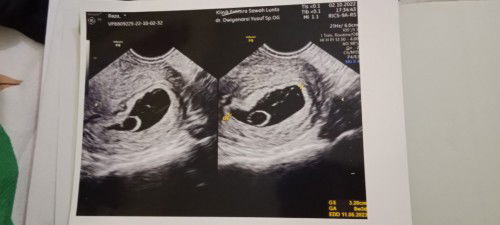

Kehamilan 8week lebih tp janin masih belum terlihat

Bund, saya semalam abis usg trs hasilnya menunjukkan bahwa janin saya masih belum terlihat bahkan menurut dokter diklinik ini menyatakan bahwa janin saya tidak berkembang dan harus dilakukan tindakan kuret.. Tp td pagi saya kontrol kembali ke puskesmas tempat saya biasa kontrol sambil saya bawa hasil usg semalam dan dokter puskesmas memberi rujukan agar di cek ulang ke rsud untuk memastikan apakah benar janinnya tidak berkembang atau berkembang tp perkembangan janinnya lambat krna yg dokter puskesmas lihat di hasil usg nya itu sudah ada bakal janinnya jd dokter tidak ingin buru2 mengambil tindakan kuret, khawatir di 1-2 minggu kemudian janinnya baru terlihat.. Ada yg mengalami hal serupa kah bund? Boleh sharing pengalamannya bund apa aja yg bunda lakukan saat ada diposisi saya? Terimakasih sebelumnya ya bund.. #seriusnanya #bantusharing #ingintahu #firstmom #pleasehelp #firstbaby